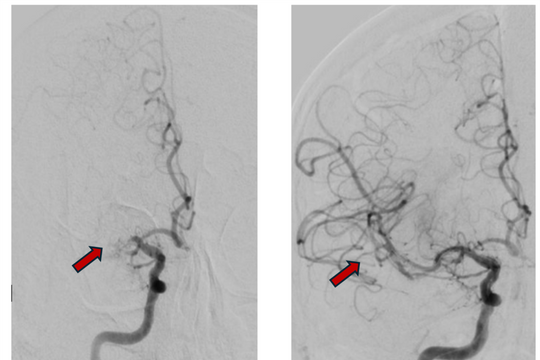

Trước diễn tiến nguy kịch, kíp bác sĩ Khoa Ngoại thần kinh phối hợp với Khoa Gây mê hồi sức đã thực hiện ca mổ cấp cứu mở sọ, lấy máu tụ và giải áp nội sọ, giúp giữ được sự sống cho bệnh nhi. Sau phẫu thuật, bệnh nhi tiếp tục được chụp mạch máu số hóa xóa nền (DSA), phát hiện dị dạng mạch máu phức tạp kèm túi phình có nguy cơ tái xuất huyết cao.

Ca phẫu thuật thứ hai sau đó được tiến hành nhằm triệt để loại bỏ toàn bộ dị dạng và túi phình. Nhờ sự phối hợp nhịp nhàng giữa các chuyên khoa, bệnh nhi phục hồi tích cực, tỉnh táo, vận động tứ chi gần như bình thường.